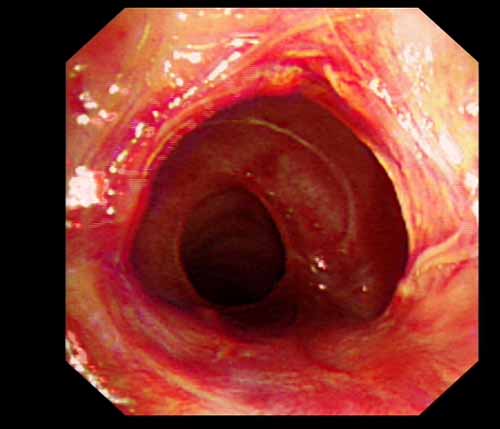

患者李某某,女,45歲,因氣管插管咳嗽、喘憋10天入院。頸部CT檢查示聲門(mén)下約20mm處氣管明顯狹窄,狹窄段長(zhǎng)約26mm,最窄處直徑約4.4mm。支氣管鏡檢查見(jiàn)聲門(mén)下約2cm氣管呈漏斗狀縮窄,直徑約4-5mm,支氣管鏡無(wú)法通過(guò)。經(jīng)科室討論,決定行電子支氣管鏡下氣管球囊擴(kuò)張治療。與患者及家屬充分溝通并經(jīng)三方見(jiàn)證談話簽署知情同意書(shū)后,在患者持續(xù)吸氧、局麻下,科主任于世倫主任醫(yī)師帶領(lǐng)治療小組為患者實(shí)行電子支氣管鏡下氣管球囊擴(kuò)張術(shù)。手術(shù)過(guò)程順利,出血量很少,術(shù)后患者呼吸困難癥狀即可明顯緩解。10天后行二次擴(kuò)張,患者日?;顒?dòng)無(wú)明顯喘憋,二次術(shù)后5天出院。

術(shù)前聲門(mén)下的漏斗樣狹窄口 術(shù)中球囊擴(kuò)張 術(shù)后擴(kuò)張開(kāi)的氣管管腔